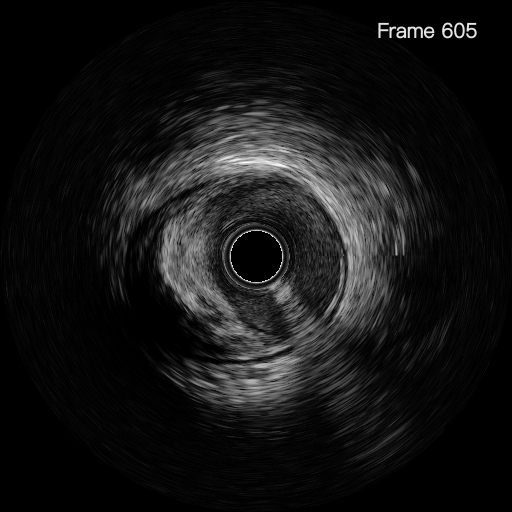

李怡教授使用该系统成功指导了一例前降支次全闭塞病例的PCI治疗。术中李怡教授通过IVUS细致地观察了患者前降支的近中段病变部位,在高清图像下对病变部位的管腔面积与斑块负荷等信息作出了详细的分析,并在成功为患者植入支架后,进一步对支架的植入效果进行了全面的评估及优化。李怡教授表示60MHzIVUS导管所生成的高清图像及管腔智能识别技术的辅助,给手术医生创造了更高效的读图分析环境,其功能的精准程度超出预期,令人印象深刻。

术前

北芯IVUS智能识别技术